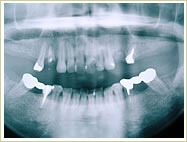

●すべての歯を失った場合

79歳 男性 インプラント埋入数:12本 画像拡大

治療前